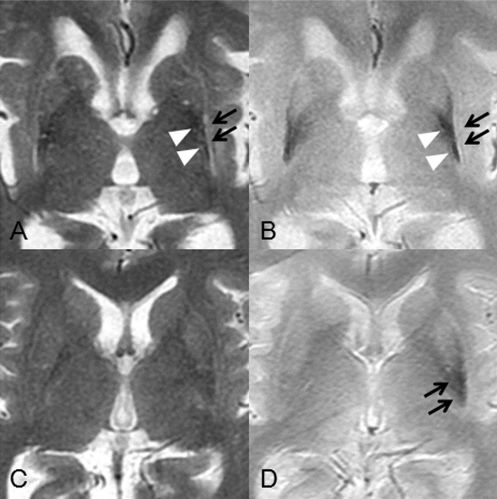

正常情況下燕尾征-SWI 的顯示:從上至下連續(xù) 1-5 層,黑質(zhì)(SN)出現(xiàn) 5 層,紅核(RN)出現(xiàn) 4 層,黑質(zhì)背外側(cè)部高信號一般位于位于黑質(zhì)的后 1/3,在紅核最后一層或消失的層面出現(xiàn)。

PD、MSA 和 PSP 出現(xiàn)燕尾征-SWI 高信號的消失

燕尾征-SWI 高信號的消失對于鑒別神經(jīng)退行性變和非退行性病變可能具有意義,但是對于鑒別帕金森病與帕金森綜合征還是缺乏準確性的。